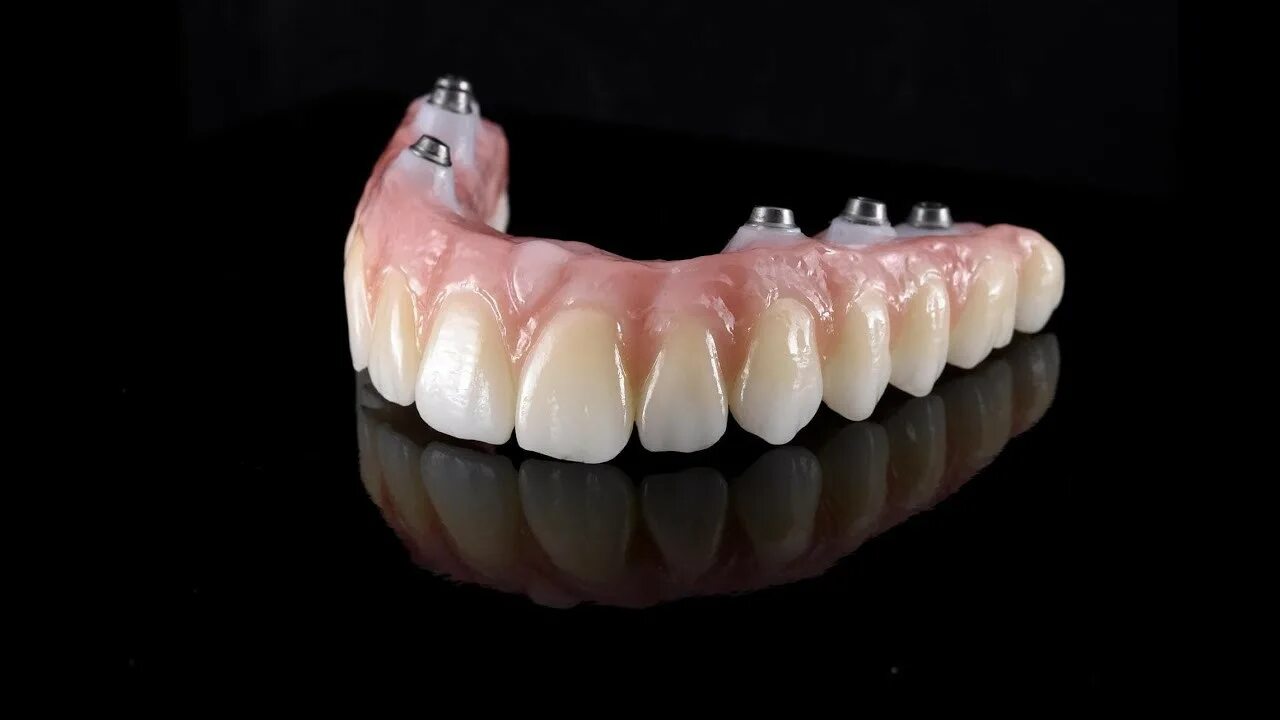

Ол он 4